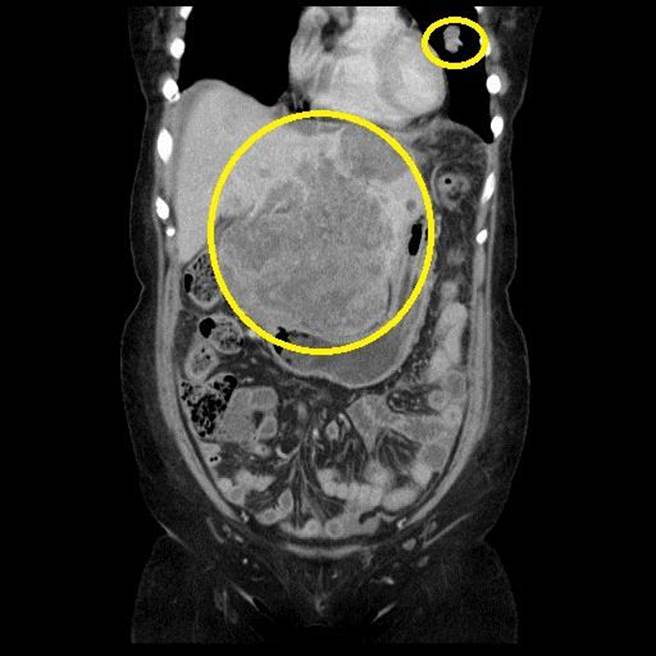

肝癌病患蔡婦術前電腦斷層,可見肝臟巨大腫瘤、散在性小顆腫瘤及上方肺部轉移病灶。(台中慈濟醫院提供/王文吉台中傳真)

蔡婦長期腹痛一直以為是胃痛,去年1月摸到肚子的硬塊就醫。台中慈濟醫院一般外科主任余政展觸診覺得不對勁,透過超音波看到巨大肝腫瘤,安排緊急檢查,病人才知道是罹患C肝進而引發肝腫瘤,再由電腦斷層確認肝腫瘤已擴散到肺部,有多發性肺轉移與肺動脈栓塞。

余政展指出,病人胎兒蛋白高達4萬多(ng/mL),肝腫瘤位置與大小不適合動刀手術。蔡婦接受免疫療法搭配標靶藥物治療,首次療程結束,胎兒蛋白已降到1萬6千多,持續治療年餘,指數降到個位數,肺部腫瘤也幾乎看不見,但腹腔仍殘餘10公分腫塊。